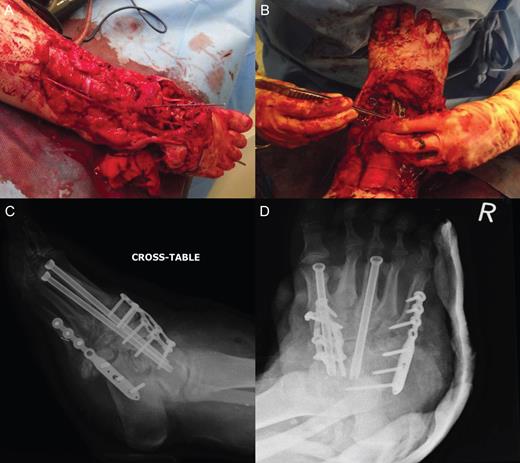

A 55-year-old woman presented with an open 3C Gustilo–Anderson fracture. Her medical history included rheumatoid arthritis, osteoarthritis, ischaemic heart disease, diabetes mellitus and asthma. Soft tissues were closed using a free flap from the left thigh and a flap from the right lower limb. Bony injury was treated with open reduction internal fixation with screw fixation of the first and third metatarsals into the talus with restoration of the medial and middle columns achieved using cannulated screws. Additional stability was achieved by plate fixation of the medial and lateral columns (Fig. 1). The treatment was deemed successful, and the patient was discharged.

Open 3C Gustilo–Anderson injury. (A and B) Theatre images of open 3C Gustilo–Anderson fracture. (C and D) Radiographs illustrating open reduction internal fixation (ORIF) (screw fixation of the first and third metatarsals into the talus). The ORIF using cannulated screws allowed restoration of the medial and middle columns of the foot. Plate fixation of the medial and lateral column was conducted to achieve additional stability.